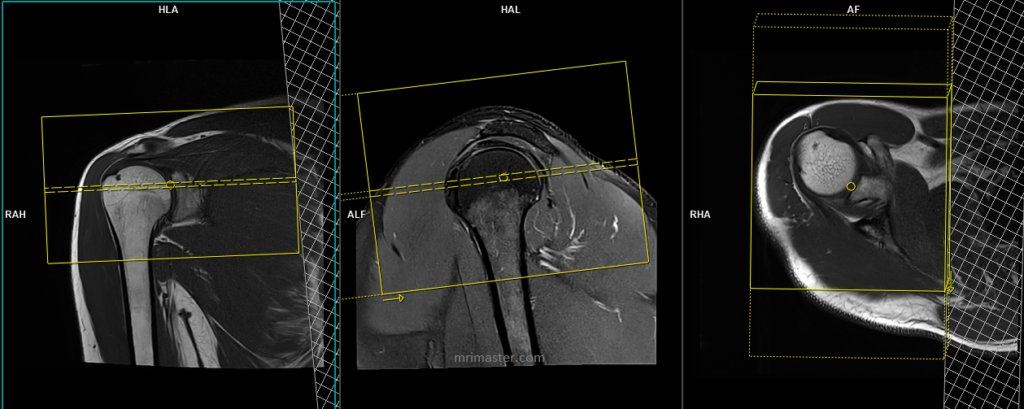

T2* medic or PD fat sat axial 3mm SFOV

Plan the axial slices on the coronal plane and angle the positioning block perpendicular to the glenohumeral joint. Check the positioning block in the other two planes. Use an appropriate angle in the sagittal plane, perpendicular to the humeral head. The slices should be sufficient to cover the entire shoulder joint from the top of the acromioclavicular joint to two slices below the inferior glenohumeral ligament (articular capsule). Adding saturation bands over the chest will help reduce ghosting artifacts caused by breathing. The phase direction should be anteroposterior to avoid wrap-around and ghosting artifacts from the chest.

Parameters pd fs

TR 3500-4500 | TE 30-40 | SLICE 3 MM | FAT SAT SPAIR | PHASE A>P | MATRIX 320X320 | FOV 150-160 | GAP 10% | NEX(AVRAGE) 2 |

Parameters medic

TR 1000-1200 | TE 30 | SLICE 3 MM | FLIP 40 | PHASE A>P | MATRIX 320X256 | FOV 150-180 | GAP 10% | NEX(AVRAGE) 2 |